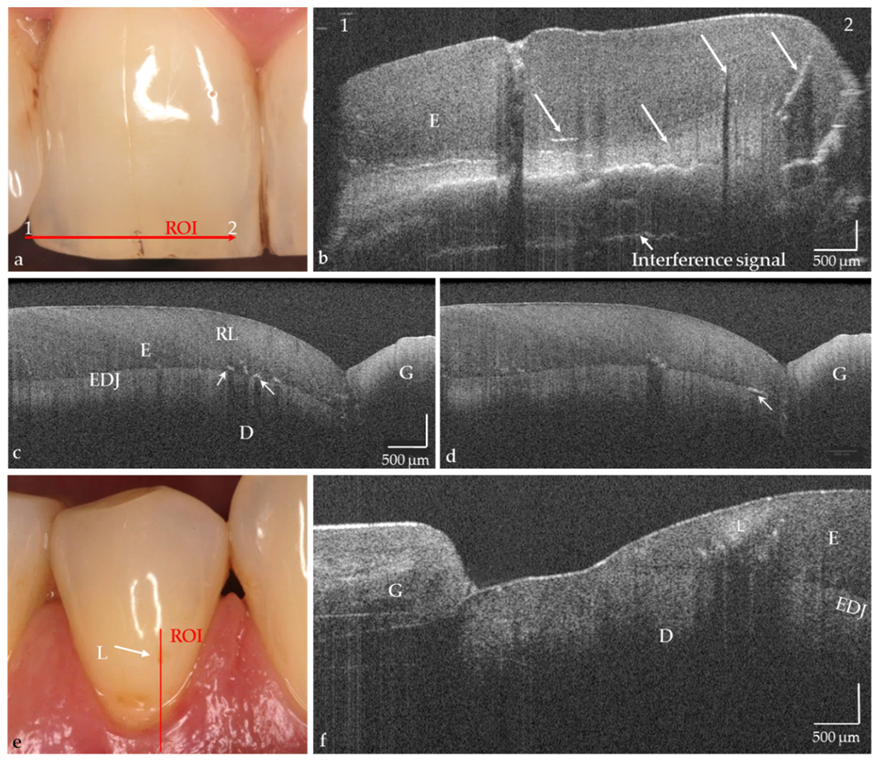

The hard tooth tissues enamel, dentin, and cement, including intrinsic structures such as Retzius lines or defects, could be imaged both on the phantom head and intraorally (Figure 4a–d, in vivo). The cross-sectional OCT images were comparable to those obtained with the laboratory probe. Early carious lesions and their dimensions were displayed in vitro and in vivo, whereby discolorations and demineralized zones could also be distinguished (Figure 4e,f). Micro-cavitations in the enamel could be verified in vitro (Figure 5).

Figure 4.

In vivo imaging of hard tooth tissues (a–f), intrinsic structures, and defects in enamel ((b–d), arrows). Partially also Retzius lines (RL; (c)) and superficial tissue structures of the gingiva (f) are indicated. (e) Premolar with vestibular brown discoloration. The OCT cross-sectional image (f) showed that besides the discoloration a carious lesion in enamel (L) is present. The lesion body appears as a bright zone with clear shadowing. Scales are related to refractive index n = 1.0. While the horizontal scale in an OCT cross-sectional image is independent of the refractive index (n) of the tooth structures, the length of the vertical scale has to be divided by it (mean n for enamel and dentin approx. 1.5). Enamel (E), dentin (D), enamel-dentin junction (EDJ), gingiva (G), region of interest (ROI).